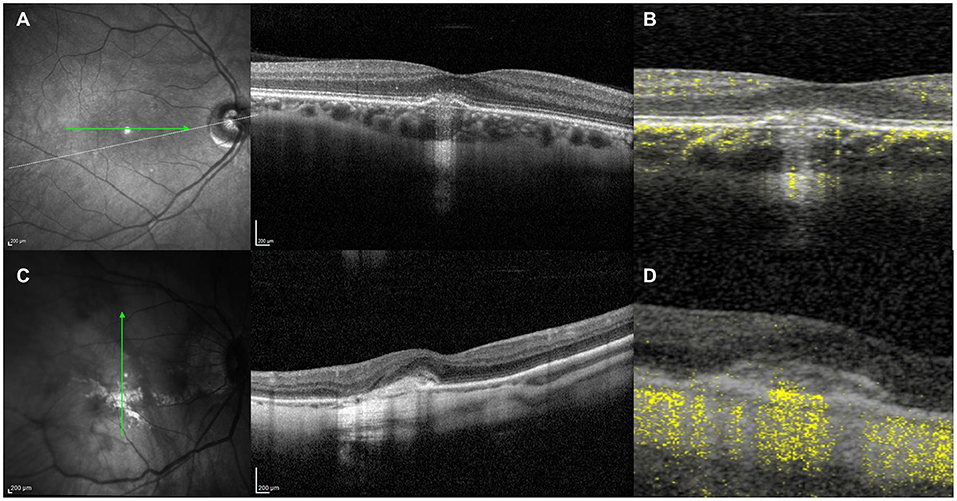

Thus, the differentiation of neovascularization and inflammation by FA might be challenging (21). The pitchfork sign is a distinctive finding in CNV with inflammatory etiology (28), described as the presence in OCT structural images of multiple finger-like projections arising from the area of CNV into the outer retina (Figure 7). Optical coherence tomography angiography (OCT-A) is an essential tool to differentiate accurately between inflammation and neovascularization in cases with subretinal exudation (Figure 8) by ruling out or confirming the presence of flow signal within the structural abnormality (21, 29).

Figure 8. (A) Structural optical coherence tomography (OCT) scan showing typical signs of an acute inflammatory lesion in a 41-year-old myopic female with central vision loss including focal retinal pigment epithelium (RPE) disruption with elevation of the borders leading to underlying choroidal hypertransmission, associated with subretinal hyperreflective material and disruption of the overlying external limiting membrane (ELM) and photoreceptors ellipsoid zone. (B) Structural OCT scan with flow signal overlay as analyzed by OCT-Angiography (OCT-A) ruling out the presence of flow signal within the inflammatory lesion, which allows to discard the presence of choroidal neovascularization. (C) Structural OCT scan showing signs of exudation with high-density subretinal material in a 52-year-old myopic female with previous history of multifocal choroditis. (D) Structural OCT scan with flow signal overlay as analyzed by OCT-A confirming the presence of flow signal within the subretinal hyperreflective tissue, suggestive of choroidal neovascularization.